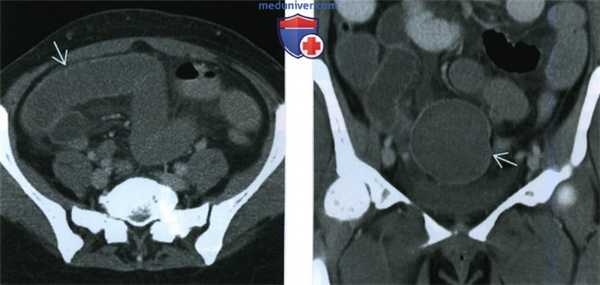

(Слева) При КТ с контрастным усилением в аксиальной плоскости у пациентки 57 лет, которой ранее по поводу миомы матки была выполнена гистерэктомия и которая обратилась по поводу болей в животе и рвоты, выявлены расширенные петли тонкой кишки.

(Справа) При КТ с контрастным усилением в корональной плоскости в проекции максимальной интенсивности у той же пациентки выявлено расширение тонкой кишки и объемное образование в малом тазу. Непосредственно позади объемного образования располагается место перехода расширенной кишки в отрезок ее с нормальным диаметром. Во время операции оказалось, что тонкую кишку сдавливала перекрутившаяся «паразитирующая» миома матки.